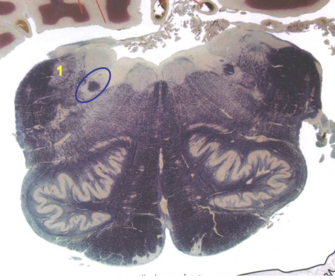

| Superior cerebellar peduncle | |

| Dentate nucleus | |

| Fastigial nucleus | |

| Anterior spinocerebellar tract | |

| Spinal nucleus of V | |

| Spinal tract of V | |

| Middle cerebellar peduncle | |

| Superior vestibular nucleus | |

| Medial lemniscus | |

| Trapezoid body | |

| Ventral trigeminothalamic tract | |

| Superior olive | |

| Longitudinal pontine fibers (corticospinal tract) | |

| Transverse pontine fibers (dark fibers) | |

| Pontine nuclei (pale) | |

| Central tegmental tract | |

| ALS | |

| Medial longitudinal fasciculus | |

| Principle nucleus of V | |

| Mesencephalic V tract | |

| Trigeminal root fibers | |

| Motor nucleus of V | |

| Cerebellar vermis | |

| Lateral lemniscus | |